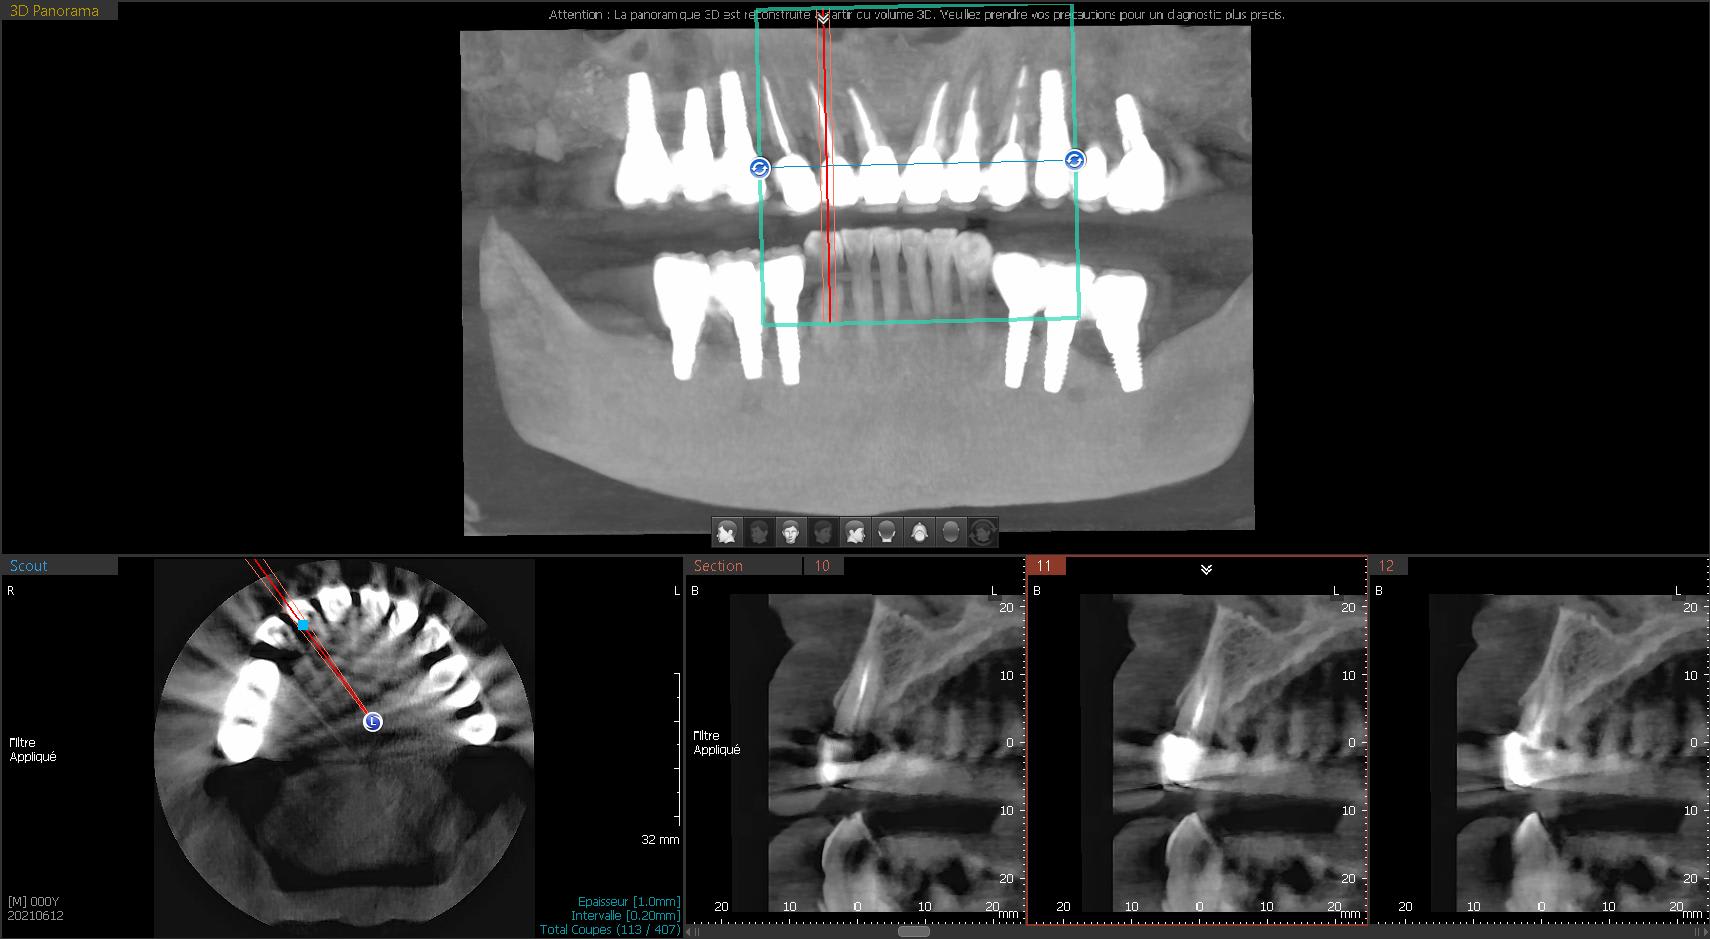

je vais entamer ma première MCEI de 13 à 23 .

J'ai choisi comme schéma la pose en 13 12 22 23 , en 11 et 21 la présence du paquet vasculonerveux palatin antérieur me refroidit.

4)forage le plus palatin possible et le plus apicalement (idealement du 13 mm)

5)mise en place des implants 22 12 13 23 à 40 N

juste faire attention à l'axe du forage: ne pas se faire piéger par l'alvéole.

22 et 23 ont clairement des pêches, c’est une contrindication pour une implantation immédiate, alors pour une mci, encore plus.

Enfin, on a pas tout le dossier, mais c’est vrai que je ne pense être parti directement sur ce plan de traitement. Peut-être plutôt, nouvelle couronne sur 23 ou extraction puis implant en temporisant avec une couronne en extension sur 22. En même temps, résection apicale pour 22 et les autres s’il faut. Et surtout , reprendre les deux secteurs postérieurs mandibulaires. ( extraction de 18, aussi, ça fait négligé sur la pano...).